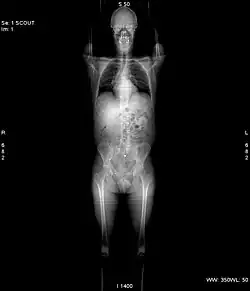

Die Übersichtsaufnahme, Topo, Scanogramm oder auch Scout-View genannt, dient lediglich der Untersuchungsplanung.

Vor jeder Aufnahme wird grundsätzlich eine Übersichtsaufnahme aufgenommen. Hierbei steht die Röntgenröhre still. Der Patient wird mit Hilfe des verfahrbaren Tisches am Fächerstrahl der Röhre vorbeigefahren. Im Ergebnis erhält man ein Bild, das einer klassischen Röntgenaufnahme sehr ähnlich sieht. Dieses Bild dient jedoch nur der Planung anschließender Aufnahmen.[1]